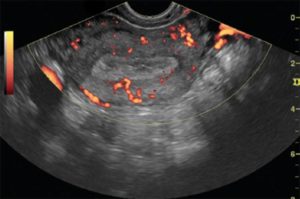

- допплерография;

При гиперплазии эндометрия УЗИ проводится с целью изучения изменений, которые произошли в маточной полости, уточнения толщины эндометрия с выявлением очагов патологии и нахождения полипов. Исследование производится специальным датчиком, который вводят женщине во влагалище.

Признаки гиперплазии эндометрия? По УЗИ проявляются его достаточно равномерным утолщением, однородной эхогенностью и ровными контурами. Для полипов характерными признаками являются новообразования, которые имеют повышенную акустическую плотность, ровные контуры и эхонегативный ободок.

Если же полипы претерпевают злокачественные изменения, ободок полипа имеет изрезанный контур.

Полипы на УЗИ — новообразования с четкими контурами, тонким эхогенным ободком и высокой акустической плотностью. Если выявляются злокачественные изменения, им присуща неравномерность контуров и неоднородная эхогенность.

Чтобы определить тип гиперплазии и проконтролировать, насколько помогает лечение, делают УЗИ на 5-7-й день месячного цикла. Точность исследования выявленных гиперпластических трансформаций составляет 90%, а обнаруженных полипов эндометрия – 60-80%.

Информативность скринингового метода может быть различной, что зависит от рабочих характеристик самого аппарата, опыта врача-диагноста и возраста больной. Эхографические признаки гиперплазии эндометрия включают ниже перечисленные:

- полипы размером 16,1-17,5 мм

- срединная маточная структура толщиной от 14,6 до 15,4 мм

- аденокарциному подозревают при показателях 19,7-20,5 мм

Гиперплазия в постменопаузальный период диагностируется, если величина М-эхо 5 и выше миллиметров.

О гиперплазии эндометрия говорят такие эхографические симптомы как ровность/неровность контура М-эхо, повышенная звукопроводимость, включение эхонегативных либо эхопозитивных структур, неоднородность эндометрия, измененный рельеф слизистой оболочки матки.